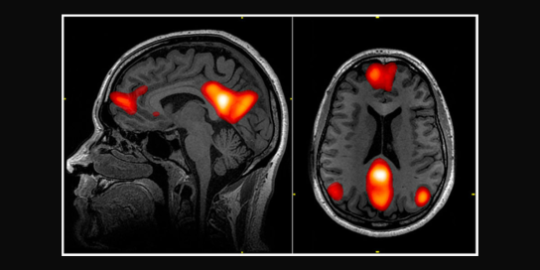

Phineas Gage Phineas Gage While you might have heard otherwise, it is not true that we only use 10% of our brain. As a matter of fact, we use all of it but at different moments. Different parts of the brain take charge of different tasks. Therefore if we are running while being silent, the area of the brain in charge of speech will not be working, while the movement area will be very busy. Determining which areas are in charge of each task is quite difficult, and it gets worse with complex tasks such as storing memories or making up our personalities. Scientists in the past, however, had a very convenient approach to this problem: if they found a person with a lesion in a specific part of the brain, they could study them and figure out which function (or functions) their brain could not do, and from that they assumed that that specific region was in charge of those roles. For example, on 1848, a railroad constructor named Phineas Gage had an accident while working: an iron pole passed through his head, destroying an area known as the left frontal lobe. Phineas survived this accident, but his personality and behaviour changed drastically. For example, he transformed from an efficient hard-working and responsible person into an antisocial, disrespectful man. His general intelligence did not change, however. This incident allowed scientists to discover that the frontal lobes are our emotional control centre.